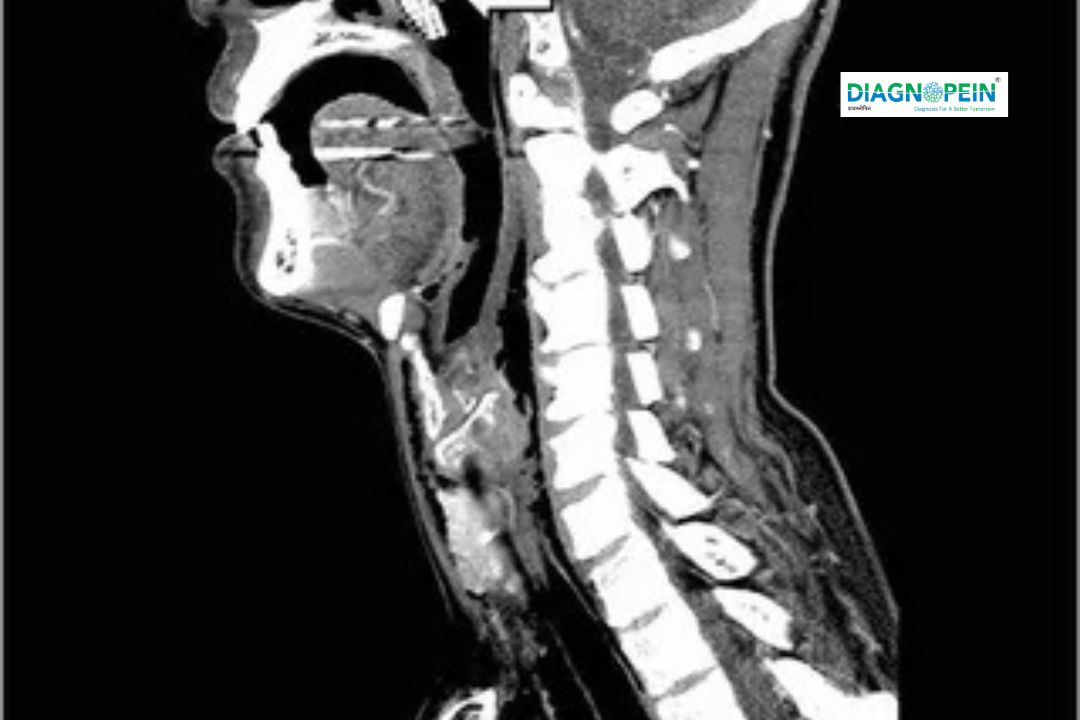

CT Neck scan is an advanced diagnostic imaging test that provides detailed, cross-sectional images of the neck’s internal structures. Using specialized X-ray technology, the scan captures clear visuals of the soft tissues, blood vessels, lymph nodes, salivary glands, thyroid, and cervical spine.

CT neck scan (Computed Tomography of the neck) is an advanced imaging test that uses X-rays to create detailed cross-sectional images of the neck’s internal structures. It helps visualize soft tissues, airways, blood vessels, thyroid gland, salivary glands, lymph nodes, and bones in the cervical region with exceptional clarity.